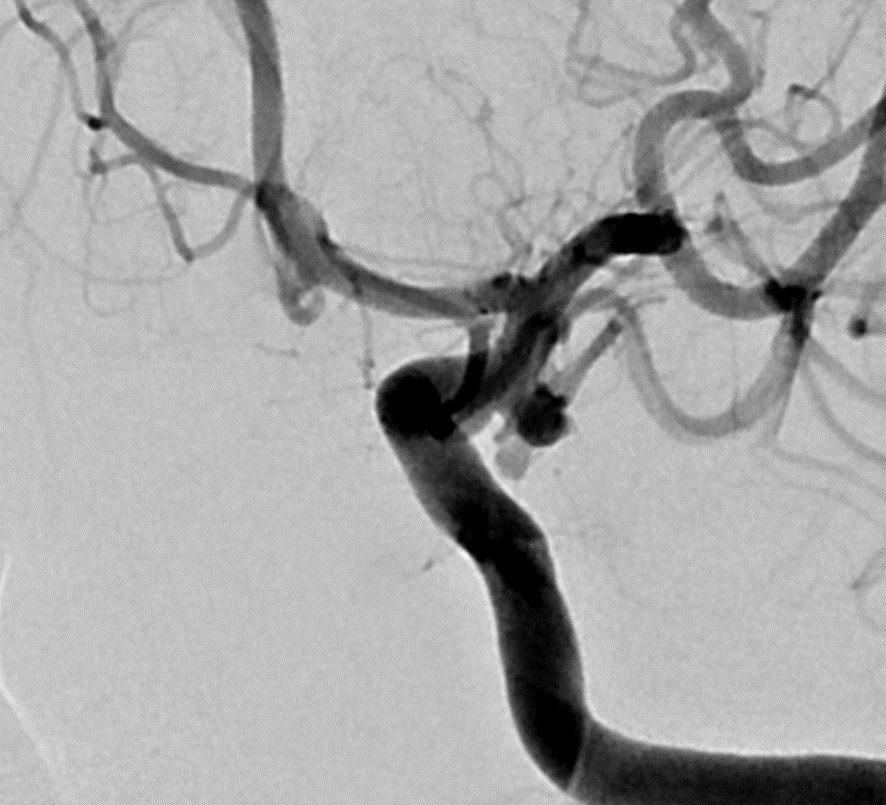

③脳動脈瘤塞栓術

脳動脈に風船のようなふくらみができることがあり、これを「脳動脈瘤」といいます。脳動脈瘤ができただけでは無症状のことが多いですが、破裂すると「くも膜下出血」となり、その瞬間に激しい頭痛が起こります。重症であれば、意識障害、片麻痺などをきたし、突然死することもあります。脳動脈瘤塞栓術は、動脈瘤の破裂を予防する目的で、血管の中から動脈瘤を閉塞する治療法です。症例:カテーテルを脳動脈瘤(黄点線内、黄矢印)の中まで誘導し、プラチナ製の「コイル」という細い金属糸を何本も入れることで、脳動脈瘤を内側より閉塞します。

症例:カテーテルを脳動脈瘤(黄点線内、黄矢印)の中まで誘導し、プラチナ製の「コイル」という細い 金属糸を何本も入れることで、脳動脈瘤を内側より閉塞します。